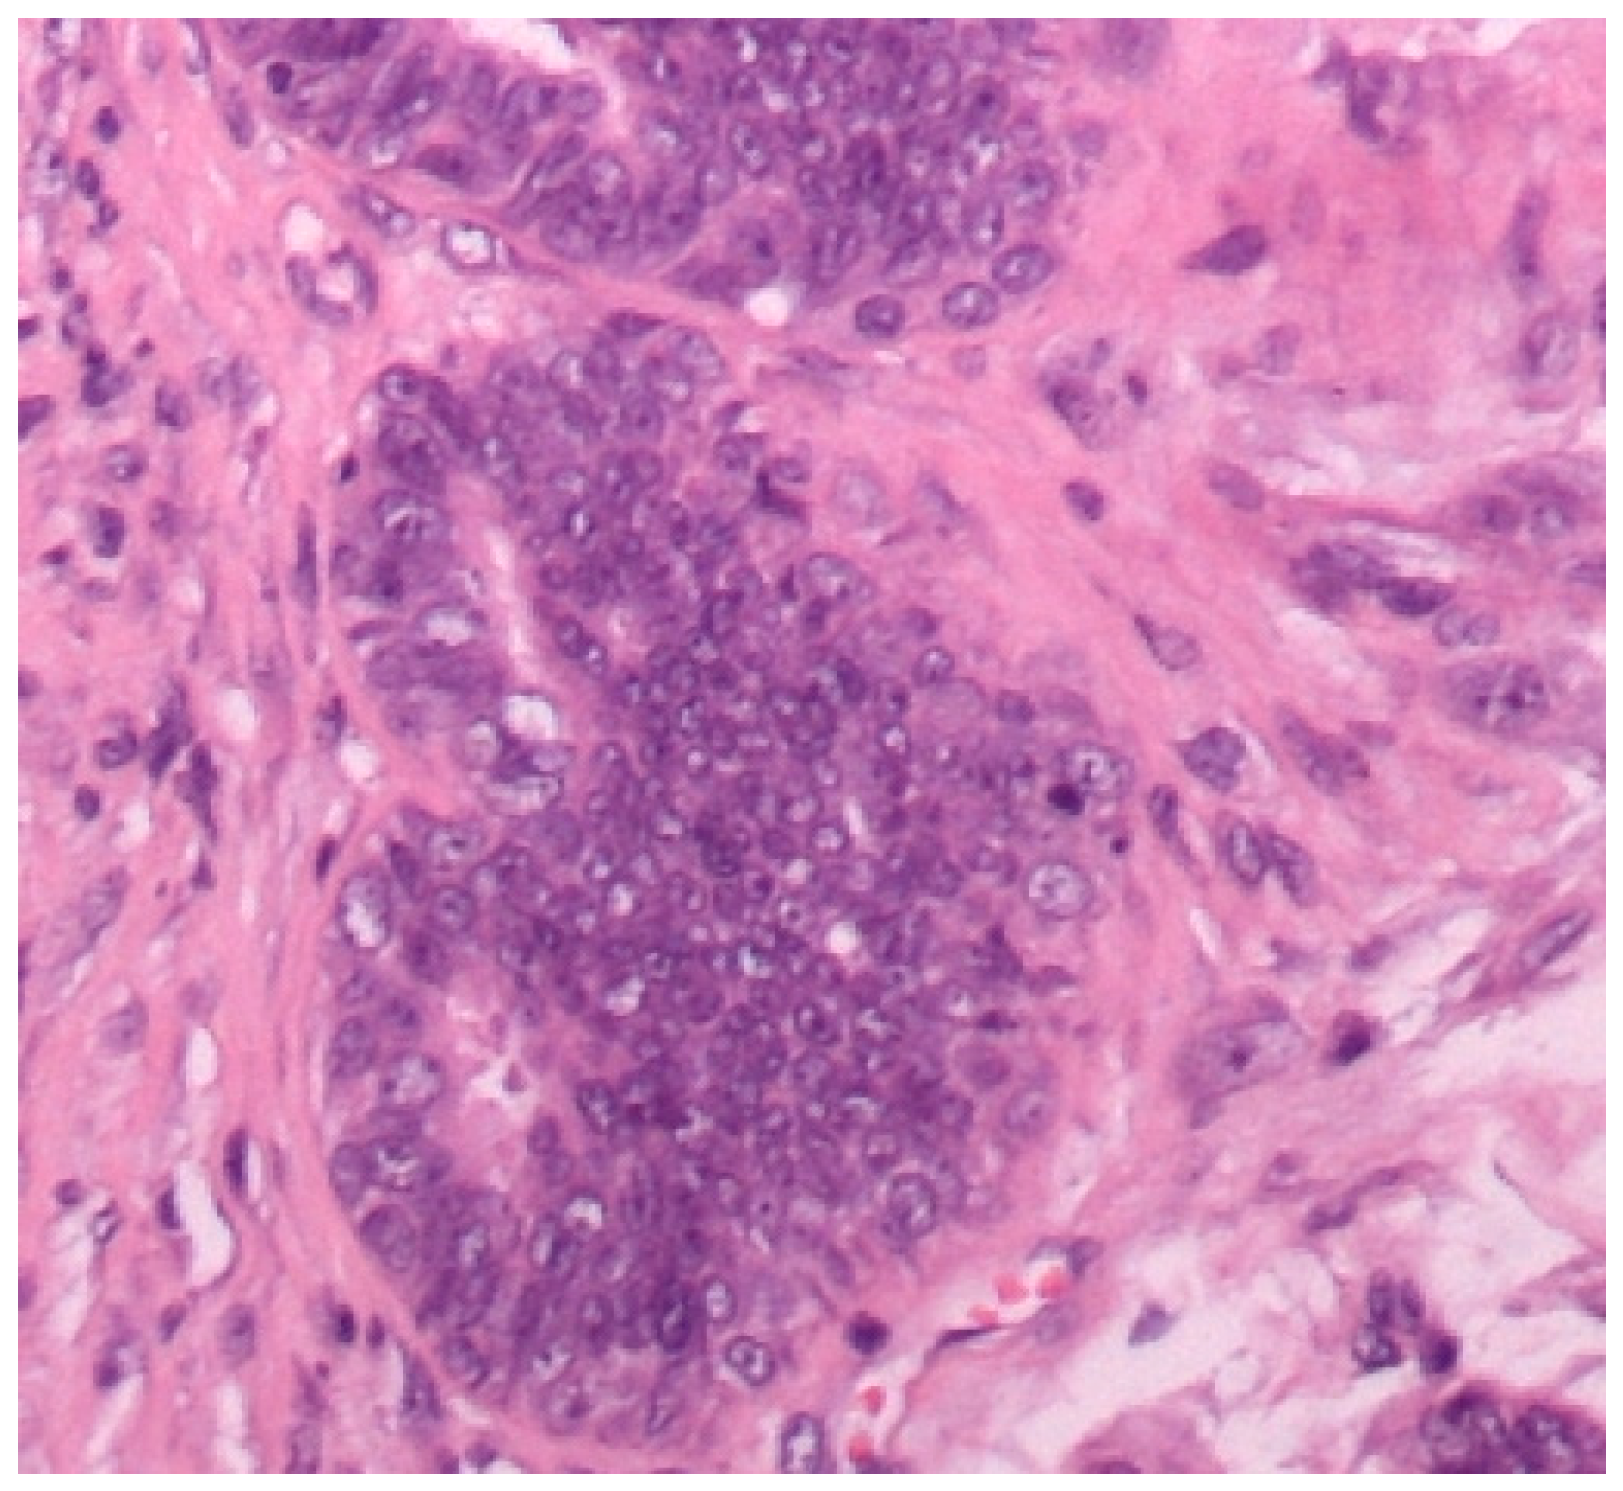

3.1. Histopathological Assessment